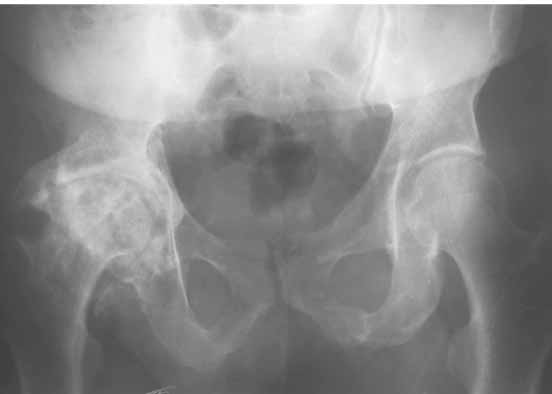

Итак: Мужчина 50 лет. Д-з: Посттравматический деф.артроз правого тазобедренного сустава с выраженным болевым синдромом, стойкой комбинированной контрактурой и укорочением 3 см. Анамнез: 10 лет назад - сочетанная травма головы, груди, конечностей, таза... перелом заднего края вертлужной впадины и вывих бедра справа. Лечился консервативно. 25.05.94 - операция тотальное эндопротезирование правого тазобедренного сустава бесцементным эндопротезом (чашка Споторно 52, ножка Вагнера 225/21, головка L), дополнительная фиксация в кокситной гипсовой повязке в течение 3 нед. Спустя месяц после операции при поворачивании на бок в кровати произошел вывих головки эндопротеза. Под наркозом вывих вправили. Вот 10 дней лежит в постели. Что необходимо делать? Рентгенограммы до операции и после. Рентгенограммы в положении вивиха у меня отсутствуют. Ну наверное они и не столь важны, ведь вывих-то вправили. Учреждение и фамилию пациента, нашего коллеги, называть не буду. Он попросил меня собрать мнения - как ему жить дальше. Заранее благодарен. С уважением Александр Артемьев